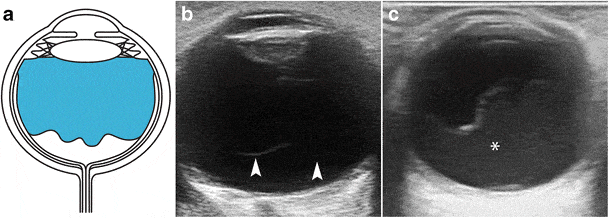

Orbita her iki göz küremizi, çevresindeki kas yapıları ve yağ dokuyu kapsayan alana verilen isimdir. Orbita ultrasonunda temel olarak göz küremizin duvar yapıları, lens, ve göz küresi içerisindeki sıvı incelenir. Göz küremizin duvarının iç tabakasına retina adı verilir. Retinal dekolman bu tabakanın yırtılıp duvardan kopması ya da tam kopmadan göz küresi içerisindeki sıvı içerisinde uzanmasını tarif eder.

Bu durumun tanısı ultasonografi ile konulur. Ayrıca sıvı içerisinde kanama olması ya da göz küresi içerisinde kitle olması durumunda da ultrason tanı koydurucudur. Göz küremizin arkasındaki kas ve yağ dokudan gelişen kitleler ve enfeksiyonlar için, gözümüzü besleyen ana atardamar ve toplar damarların incelenmesinde de ultrason gereklidir.